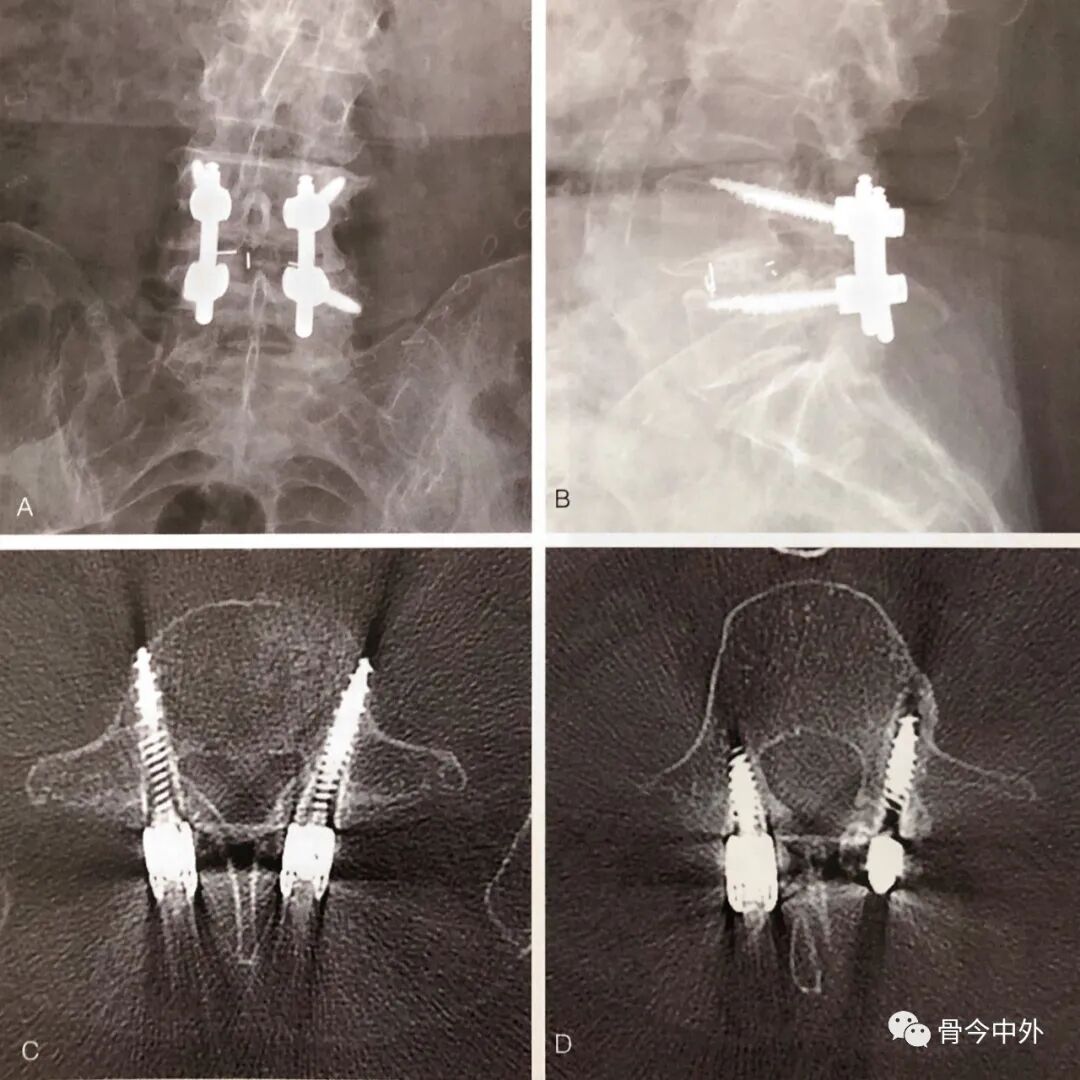

在钻孔之前和钻孔过程中,使用C臂透视,以确认进钉点和钉道方向。用直径2mm的高速钻头去除进钉点皮质。钻孔期间,经常停下来,使用球探探查钉道的底部,以明确钉道末端位于皮质骨内。正侧位透视,确定螺钉钉道正确。钻头尖端缓慢进入约30mm,攻丝之前,球探探查,确定钉道完整。攻丝后,再重新检查钉道,明确钉道完整后,植入直径5.0mm或5.5mm的皮质骨螺钉。同法植入其他螺钉(图3)。

图3 术后正位(A)和侧位(B)X线片显示L4和L5椎体的皮质骨螺钉固定,横断面CT成像显示同一患者L5(C)和L4(D)的皮质骨螺钉钉道。